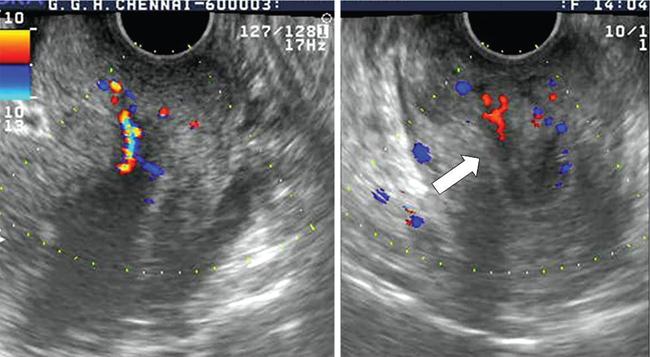

Venkatraman Indiran Bridging vessel sign Multiple vascular channels (white arrows) connecting uterus (black arrow) to an adjacent pelvic mass on imaging studies, is known as the ‘bridging vessel’ or ‘bridging vascular’ sign. Originally described on colour Doppler imaging, but also seen on computed tomography (CT) or magnetic resonance imaging (MRI). Helps in differentiating a mass of uterine origin, typically a subserosal fibroid, from other pelvic masses. Sensitivity and specificity of ‘bridging vessel sign’ in identifying subserosal fibroids range from 90% to 100%. (Best seen when subserosal fibroid is larger than 3 cm in diameter.) Ovarian masses invading the uterus may rarely produce a falsely positive bridging vessel sign. Broccoli sign Submucosal uterine leiomyoma prolapsing into the endocervical canal, along with its stalk in the uterine cavity on sagittal T2-weighted images together is called as ‘broccoli sign’ (white arrow). Submucosal uterine leiomyoma Bunch of grapes Intrauterine mass with cystic spaces without any associated foetal parts on ultrasound (white arrows) classically gives a ‘snow storm’ or ‘bunch of grapes’ appearance. Complete hydatidiform mole Hourglass sign Deep infiltrating endometriosis (DIE) affecting the posterior urinary bladder wall, usually in the midline, causes loss of its distensibility, resulting an hourglass configuration of urinary bladder. Deep infiltrating endometriosis (DIE) Hyperechoic line sign Normal endometrium surrounding the endometrial polyp on ultrasound appear as a hyperechoic rim on transvaginal ultrasound is called as ‘hyperechoic line sign’. Hyperechoic line sign represents a focal intracavitary lesion. Endometrial polyp Indian head dress sign/moose antler sign In deep infiltrating endometriosis (DIE), adhesions between the anterior wall of rectosigmoid and posterior wall of uterus, stretches the muscular layer of the bowel and creates an infiltrative nodule with parallel lines that extend from the adhesion to the rectosigmoid. This is called as ‘Indian head dress sign/moose antler sign’ (white arrow). This is seen on sagittal T2-weighted images as well as transvaginal ultrasound. Deep infiltrating endometriosis (DIE) Interstitial line sign An echogenic line that extends into the upper regions of the uterine horn and borders the margin of the intramural gestational sac is called as the ‘interstitial line sign’ (white arrow). Seen best on transabdominal/transvaginal ultrasound. Specific finding of interstitial pregnancy Mushroom cap sign Mushroom-shaped lesion which is seen displaced into the bowel lumen in patients with solid invasive endometriosis of the rectosigmoid colon on axial or sagittal T2-weighted MRI is called as ‘mushroom cap sign’ (red box and white arrow). Low signal intensity base of the mushroom corresponds to hypertrophy and fibrosis of the muscularis propria, whereas the high intensity cap represents oedematous mucosa and submucosa. Deep infiltrating endometriosis (DIE) Pedicle artery sign Feeding vessel sign Central vessel entering the endometrium from the surrounding myometrium colour Doppler imaging of the endometrium in endometrial polyps is called as pedicle artery sign (white arrow). Endometrial polyps in women with postmenopausal bleeding. (Sensitivity of 76.5%; specificity of 95.3%.) Popcorn ball calcification Dense, amorphous calcifications of uterine fibroids seen on the plain radiographs is called as ‘popcorn calcification’ (white arrow). Confluent, coarse calcification constitutes the most specific radiographic sign of a benign uterine fibroid; but only 10% or fewer of fibroids show calcification. Question mark sign of uterus The uterine corpus that is flexed backward with the fundus of the uterus facing the posterior pelvic compartment and the cervix directed anteriorly toward the urinary bladder, is called as question mark sign of uterus (white arrow). Also called as comma-shaped uterus. 93% specificity and 75% sensitivity in diagnosing adenomyosis uterus. Sliding organs’ sign When the uterus and ovaries glide freely over the posterior and anterior organs (such as rectum and urinary bladder, respectively) during real-time dynamic transvaginal sonography, it is called as ‘positive sliding organs’ sign’. In case of adhesions due to endometriosis, free gliding of organs is absent and is called as negative sliding sign. Snowstorm sign Grainy appearance with low-level homogeneous internal echoes which move slowly downward due to their viscosity seen in endometrioma on transvaginal ultrasound is called as snowstorm sign. Endometriomas Split fibre sign Presence of curvilinear T2 hypointense strands within the degenerated leiomyoma separated by the fluid accumulation and oedema is called as the ‘split fibre’ sign. Split fibre sign on T2-weighted MRI can be used to differentiate hydropic degeneration from other conditions like malignant change. Three-line sign or triple line sign or trilaminar appearance Shortly before ovulation, two additional bright linear echoes outline two hypoechoic layers of endometrium with a central hyperechoic line in the endometrium (white arrow). It is called as the ‘three-line sign’ or ‘triple line sign’ or trilaminar appearance. A triple-line pattern with a moderate endometrial thickness is associated with a good clinical outcome on in-vitro fertilization. Venetian blind shadowing Also known as ‘rain shower’ appearance Heterogeneous myometrial appearance due to hyperechoic heterotopic endometrial tissue and hypoechoic hyperplastic smooth muscle appearing as vertical linear bands of shadows on ultrasound is called as ‘Venetian blind shadowing’. Classically described in uterine adenomyosis; sometimes in uterine fibroids also. Bead on strings sign Thickened endosalpingeal longitudinal folds within a dilated fallopian tube without wall thickening appears as small mural nodules on cross-sectional images on ultrasound is called as ‘bead on strings’ appearance. Seen in chronic salpingitis Beaded tube Multiple constrictions along the course of fallopian tube may form due to scarring is seen in genitourinary tuberculosis and shows a ‘beaded’ appearance. Female genital tuberculosis Cogwheel sign Thickened endosalpingeal longitudinal folds within a dilated fallopian tube with thickened wall appears as small mural nodules on cross-sectional images across the long axis of the fallopian tube on ultrasound (white arrows) produce a characteristic ‘cogwheel’ appearance. Seen in acute salpingitis. The presence of thickened longitudinal folds is pathognomonic for hydrosalpinx. Cobblestone tube Rounded filling defects in cases of fallopian tube tuberculosis are called as the cobblestone pattern. Is an effective radiographic sign of intraluminal scarring and adhesions. Female genital tuberculosis Golf club tube Occlusion of the isthmus or fimbrial end of the fallopian tube and filling up of the tube with serous or clear fluid produces a moderate dilatation at the fimbrial end, produces a ‘golf club–like appearance’. Female genital tuberculosis Halo sign Thin radiolucency seen separating the loculated peritubal collection from the dilated tube, is known as the ‘halo sign’. This radiolucent halo represents the thickened wall of the tube. Female genital tuberculosis Incomplete septation sign Thin linear structures appearing to protrude into the tubular cystic adnexal structures, but not touching the opposite walls is called ‘incomplete septation sign’ of hydrosalpinx. Apparent septae are due to apposition of the inner walls of the dilated and folded fallopian tube. Hydrosalpinx Pipe stem tube Rigid contour of the fallopian tube seen in cases of fallopian tube tuberculosis is called as ‘pipe stem appearance’. Female genital tuberculosis Leash sign Typical eccentric leash of vessels on colour Doppler (white arrow) showing a low resistance placental type of flow on spectral Doppler in fallopian tube ectopic pregnancies is called as leash sign.